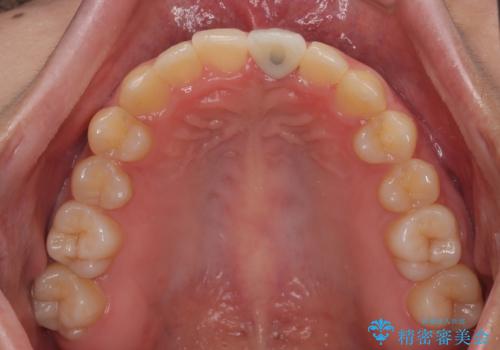

- 前歯のインプラント治療を希望して来院された患者様です。

小学生の時に前歯を殴打したとのことで、歯根が吸収してしまい、抜歯が必要と判断されました。

抜歯、インプラント埋入、仮歯の装着が同時に可能な1DAYインプラントを行いたいところでしたが、吸収による歯肉の炎症が著しいため、抜歯後に炎症が治まるまで待機し、極力早期にインプラント埋入を行うこととしました。

長い間歯肉が炎症を患っていたため、炎症改善後には歯肉がやや退縮した状態となっていました。

歯肉移植により歯肉形態を改善するプランも提案しましたが、十分な仕上がりとのことで、大変満足していただけました。